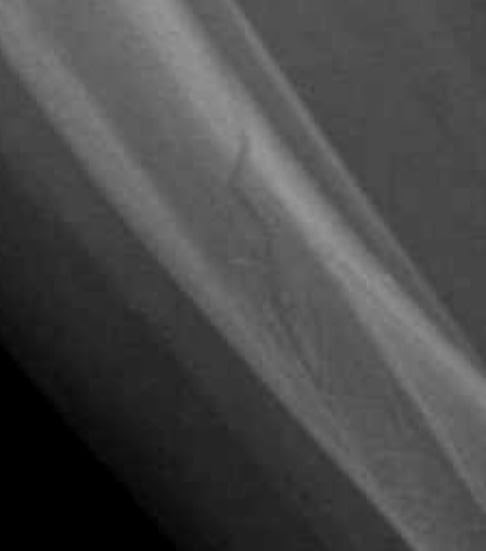

- La fracture en bois vert (fig 1-a)

Il s'agit d'une rupture corticale partielle: 1 seule corticale cède avec persistance d'une continuité cortico-périostée dans la concavité de l'incurvation induite par le traumatisme; traitement: réduction+ plâtre 6 semaines+ surveillance.

-L' incurvation traumatique (fig 1-b)

Elle est rare, c'est une déformation plastique et se traduit par une exagération de la concavité de l'os par de multiples micro-fractures, sans trait visible.

Les localisations préférentielles sont le péroné et le cubitus, avec habituellement fracture complète de l'os adjacent dont la réductibilité peut être limitée par l'incurvation.

- La fracture en cheveu (fig 1-c)

Il s'agit d'une fracture spiroïde incomplète, avec trait fin, sans déplacement. Elle est difficile à voir. Le site préférentiel est la moitié inférieure du tibia, lors de l'apprentissage de la marche.

Dans ces 2 derniers types de fractures, la lésion osseuse peut passer inaperçue sur les incidences classiques, des obliques doivent être effectués si la clinique est évocatrice d'une lésion traumatique. Si elles sont méconnues sur le bilan initial, les clichés ultérieurs montreront des appositions périostées ou un épaississement cortical et une meilleure visualisation du trait.

1a-bois vert             1b-incurvation traumatique               1c-cheveu